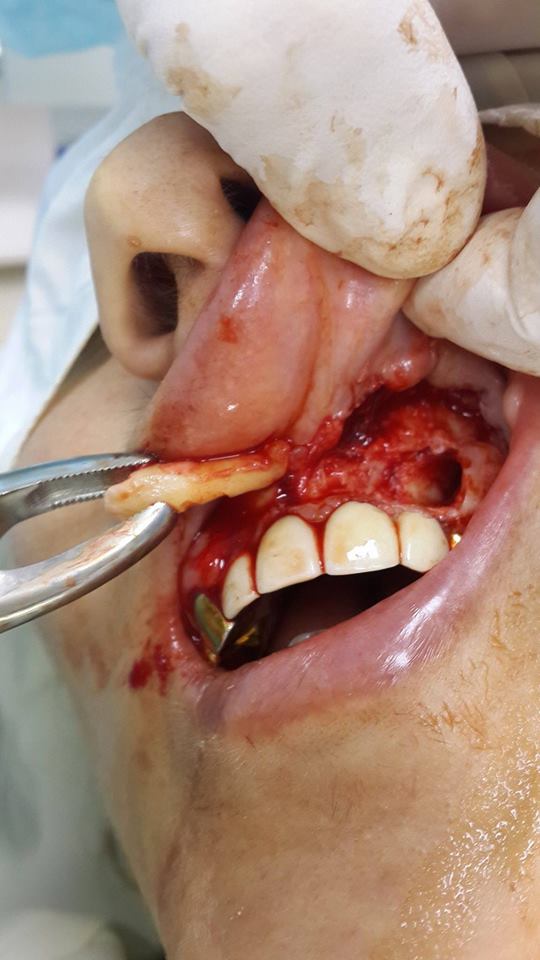

The patient turned to the doctor with the presence of a retinas tooth. The tooth was surgically removed.